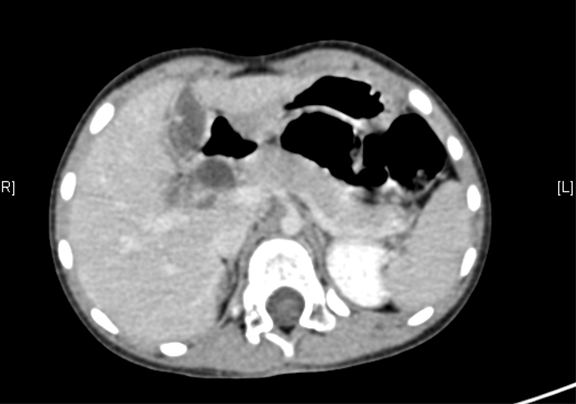

术前CT检查:

动脉期

一般情况:CH-001-CBD-000021,3岁足月产女性患儿,身高105cm,体重16.5kg,

主诉:发现胆总管扩张1月。

现病史:,患儿无明显诱因出现腹痛,无发热不伴有黄疸,在当地医院考虑"胆管扩张症",给予抗炎保守治疗好转。近一个月来患儿未出现腹痛等不良主诉,今日为求进一步诊断来我院,拟诊"先天性胆管囊肿"收入院。

腹部B超:先天性胆总管囊状扩张上腹部CT(外院):胆总管囊肿。